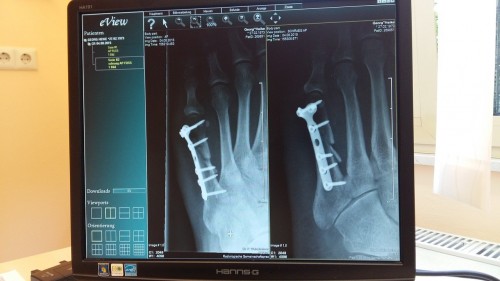

A leggyakoribb nyári gyerekbalesetek a törések és a napégés

A csonttörés, a zúzódás, a napégés, a száj- és bélfertőzés, valamint a rovarcsípés a leggyakoribb egészségügyi probléma a gyermekeknél nyáron - mondta Póta György háziorvos az M1 aktuális csatorna szombati műsorában.